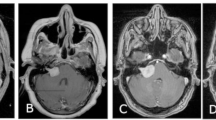

This study explores the natural history of vestibular, trigeminal and lower cranial nerve schwannomas (VS, TS, LCNS) in patients with Neurofibromatosis type 2 (NF2), to understand how pathogenic variants (PVs) of the NF2 gene affect tumour burden and growth rate, via a retrospective analysis of a UK NF2 centre database and imaging. VS, TS and LCNS location and size were measured in accordance with a standardised protocol. PVs were categorised in accordance with the UK NF2 Genetic Severity Score (GSS). 153 patients (age 5–82) had 458 schwannomas, of which 362 were previously untreated comprising: 204 VS, 93 TS, and 65 LCNS (IX, X, XI). 322 schwannomas had sequential imaging allowing growth rate analysis with a mean follow-up of 45 months. VS were universally present, and bilateral in 146/153 cases. 65% of tumours grew >2 mm during the study period at mean rate 2.0 mm/year. Significant association was found between increasing GSS and growth rate. TS occurred in 66/153 patients (bilateral in 27/153); 31% of tumours showed growth (mean 1.8 mm/yr). Significant increase in tumour prevalence was noted with increasing GSS. LCNS were found in 47/153 patients (bilateral in 19/153); 27% of tumours showed growth (mean 1.9 mm/yr). The trend for increased prevalence with increasing GSS did not reach significance. VS growth rate was significantly influenced by GSS and they were much more likely to grow than TS and LCNS. TS prevalence also correlated with increasing GSS.